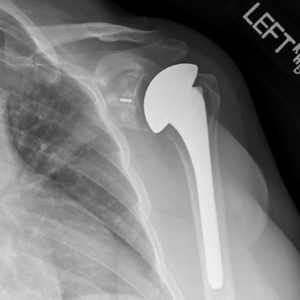

Полная замена илитотальное эндопротезирование плечевого сустава. Стержень плечевого протеза может закрепляться на цементе или бесцементно. © Gelenk-Klinik

Полная замена или тотальное эндопртезирование плечевого сустава. Стержень плечевого протеза может закрепляться на цементе или бесцементно.

Полная замена плечевого сустава

Полная замена плечевого сустава или тотальное эндопротезирование плечевого сустава. Плечевой компонент зафиксирован внутри плечевой кости. Гленоидный компонент замещает суставную впадину. © Wikipedia

При полной замене плечевого сустава заменяются оба компонента сустава: плечевая головка и суставная впадина. Это самый распространенный метод замены плечевого сустава. При износе обеих поверхностей сустава, как плечевой головки так и суставной впадины, необходим полный эндопротез. При таком методе замены удаляется сегмент плечевой головки, наиболее близкий к суставу. Затем внутренняя часть (пространство костного мозга) плечевой кости подготавливается для внедрения ножки протеза.

Ножка протеза имплантируется вовнутрь кости. Одним из наиболее тяжелых осложнений при полной замене плечевого сустава является ослабление гленоидного компонента. Это ведет к возникновению боли и ограничению подвижности.

Поэтому тщательная диагностика, оптимальный подбор размера и подгонка компонентов протеза является необходимым аспектом плечевой хирургии. Специалисты по плечевым суставам должны также детально оценить риск таких осложнений, как остеопороз (снижение плотности кости).